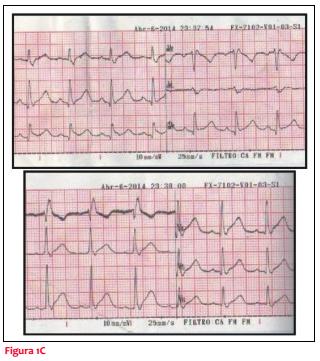

Recibe tratamiento antihistamínico intravenoso, una serie de salbutamol inhalatorio, ácido acetilsalicílico, nitritos sublinguales y suero fisiológico con mejoría en lo respiratorio y cediendo parcialmente el dolor. Se traslada a emergencia, donde se mantiene clínicamente incambiado, se administra morfina para calmar el dolor, se realiza carga de clopidogrel (300 mg), heparina de bajo peso y estatinas. Instala cambios dinámicos a nivel del ECG con ritmo sinusal y renivelación del ST en cara inferior y supradesnivel del ST de cara anterior (figura 1B).

Se solicitó coronariografía (CACG) de urgencia. Al arribo al centro de hemodinamia, a las dos horas de la consulta, se constata paciente asintomático y al examen físico: lúcido, bien hidratado y perfundido, leve eritema cutáneo en tronco, tolerando el decúbito, PA 90/50, con ritmo regular de 80 cpm, se constata soplo eyectivo mesotelesistólico con A2 disminuido, eupneico y no se auscultan estertores secos ni húmedos. Previo a la realización del estudio se realiza nuevo ECG que evidencia ritmo sinusal y renivelación del ST de cara anterior persistiendo bloqueo completo de rama derecha (BCRD) (figura 1C).